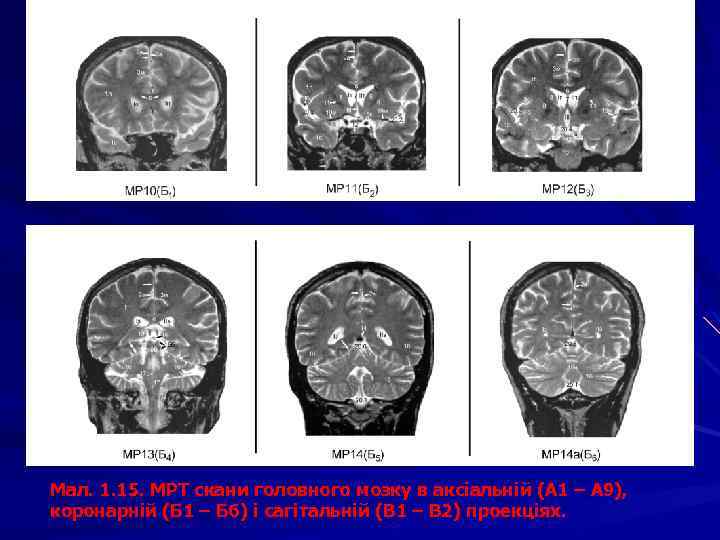

Мал. 1. 15. МРТ скани головного мозку в аксіальній (А 1 – А 9), коронарній (Б 1 – Б 6) і сагітальній (В 1 – В 2) проекціях.

Мал. 1. 15. МРТ скани головного мозку в аксіальній (А 1 – А 9), коронарній (Б 1 – Б 6) і сагітальній (В 1 – В 2) проекціях. 1 – частки великого мозку: 1 л – лобова, 1 т – тім’яна, 1 с – скронева, 1 п – потилична, 1 о – острівцева, 1 нц – напівовальний центр. 2 - щілини великого мозку: 2 а – поздовжня, 2 б – поперечна. 3 т – потилично-скронева, 3 у – каудально -таламічна, 3 ф - 3 – борозни: 3 а – центральна, 3 б – бічна, 3 в – передцентральна, 3 г – верхня лобова, 3 д – нижня лобова, 3 е – зацентральна, 3є – нюхова, 3 ж –потиличні, 3 и – шпорна, 3 з – півмісяцева, 3і – верхня скронева, 3ї – нижня скронева, 3 к – острівцеві, 3 л – мозолистого тіла, 3 м – поясна, 3 н – підтім’яна, 3 н – нижня тім’яна, 3 о – тім’яно-потилична, 3 п – каудально-таламічна, 3 р – гіпокамп 3* звивини: 3 а* – передцентральна, 3 б* – зацентральна, 3 в* – верхня лобова; 3 г* – середня лобова, 3 д* – нижня лобова, 3 ж*– верхня скронева, 3і* – середня скронева; 3 и* – нижня скронева; 3 к* – верхня тім’яна часточка, 3 л* – нижня тім’яна часточка; 4 – шлуночки мозку: I, ІІ – бічні шлуночки: п – передній, з – задній, н – нижній роги, с – судинне сплетіння, т – тіло; III шлуночок: з – зорова, л – лійкова заглибини; с – міжталамічна спайка, о – міжшлуночкові отвори; IV шлуночок: б – бічний, с – серединний отвори. 5 – водопровід мозку. 6 – мозолисте тіло: 6 в – валок, 6 с – стовбур, 6 к – коліно, 6 д – дзьоб, 6 п – променистість; 6* – передня комісура (спайка). 7 – прозора перегородка: 7 п – порожнина прозорої перегородки. 8 – хвостате ядро. 9 – таламус, 9* – гіпоталамус. 10 – смугасте тіло. 11 – внутрішня капсула: 11 п – передня ніжка, 11 з – задня ніжка, 11 к – коліно. 12 – гіпофіз. 13 – зорове перехрестя. 14 – шишкоподібне тіло. 15 – ніжка мозку, 15 а – червоне ядро, 15 б – горбки чотиригорбистості. 16 – мозочок: 16 ч – черв ’як, 16 м – мигдалик, 16 я – ядра. 17 – довгастий мозок, 17 ц – центральний канал. 18 – міст. 19 – кровоносні судини, 19 А – мозкові артерії: 19 а – передня, 19 m – середня, 19 p – задня; 19 v – вертебральна, 19 k – сонна, 19 c – мозочкова; 19 V – мозкові вени: 19 iv – внутрішня вена мозку; 19 vj – велика вена (Галена); 19 S – синуси: 19 r – прямий, 19 ks – стік синусів, 19 ss – сагітальний синус. 20 – цистерн підпавутинного простору: 20. 1 – мозочково-довгаста (бульбарна); 20. 1 а – валекула; 20. 1 м – верхня мозочкова; 20. 2 – бічної ямки великого мозку; 20. 3 – міжніжкова; 20. 4 – зорового перехрестя; 20. 5 – навколомозолиста; 20. 6 – великої вени (чотиригорбистості); 20. 7 – оточуюча; 20. 8 – мосто-мозочкова; 20. 9 – цистерни моста; 20. 10 – конвекситальний субарахноїдальний простір. Присінковозавитковий нерв – позначено*, мозочковий серп – стрілкою, мозочковий намет – подвійною стрілкою. 21 – кістки черепа: 21 р – решітчаста, 21 л – лобова, 21 к – клиноподібна, 21 тс – турецьке сідло, 21 т – тім’яна, 21 п – потилична, 21 с – скронева, 21 сх – схил. 22 – ламбдоподібний шов. 23 – великий потиличний отвір. 24 - орбіта.